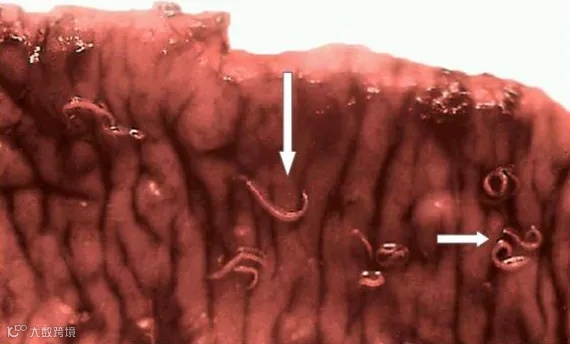

毛尾线虫病(鞭虫病)

由毛尾科毛尾属线虫寄生于大肠(尤以盲肠为主)所致,因虫体前细后粗形似鞭而得名。主要病原为羊毛首线虫,亦见兰氏毛尾线虫等;幼畜易感,重度感染可致死亡。